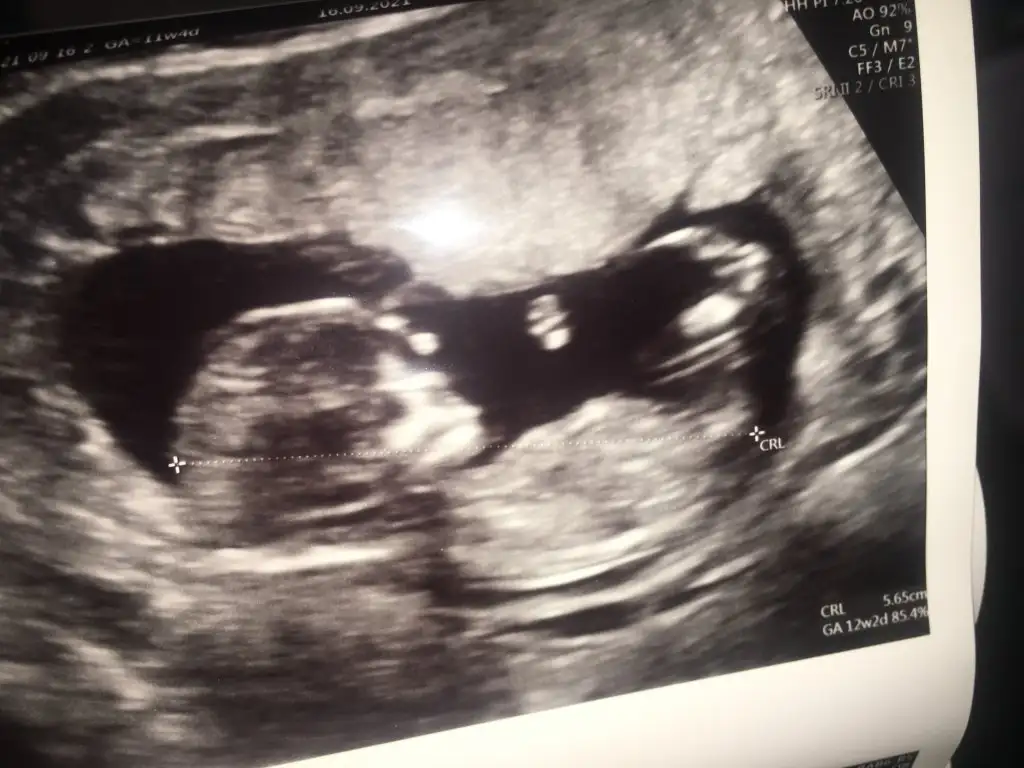

Merhaba arkadaşımın ultrason görüntüsüne bakar mısınız? 10. Hafta ve 12. Hafta ultrasonları.Teşekkürler

• 7FF8643E-BB02-4391-8D0B-2E1F0B581712.webp

7FF8643E-BB02-4391-8D0B-2E1F0B581712.webp

23,5 KB · Görüntüleme: 101

• 014BC34E-EE88-45F6-AFA3-2832026F3BE4.webp

014BC34E-EE88-45F6-AFA3-2832026F3BE4.webp

10 KB · Görüntüleme: 90